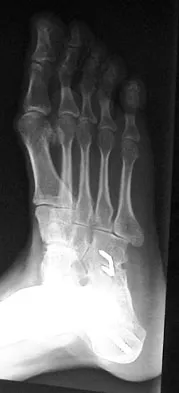

A 45-year-old woman has had intense pain in her foot for the last 3 days. She also reports a mild fever and difficulty with shoe wear. Examination reveals a swollen, slightly erythematous warm foot with tenderness at the great toe metatarsophalangeal joint and pain with passive motion of the joint. An AP radiograph is shown in Figure 13. Which of the following will best aid in determining a definitive diagnosis?

Explanation

The patient has gouty arthropathy of the first metatarsophalangeal joint. This definitive diagnosis is achieved with aspiration of the joint and polarized light microscopy that shows needle-shaped negatively birefringent monosodium urate crystals. Differential diagnoses of infectious arthritis and pseudogout are also definitively made through joint aspiration. Although rheumatoid arthritis is a possibility, a serum rheumatoid factor is not always diagnostic and a patient with rheumatoid arthritis may have concomitant gouty arthritis. The radiographic findings are not typical of diabetes mellitus or of a patient with Charcot arthropathy. Wise CM, Agudelo CA: Diagnosis and management of complicated gout. Bull Rheum Dis 1998;47:2-5.